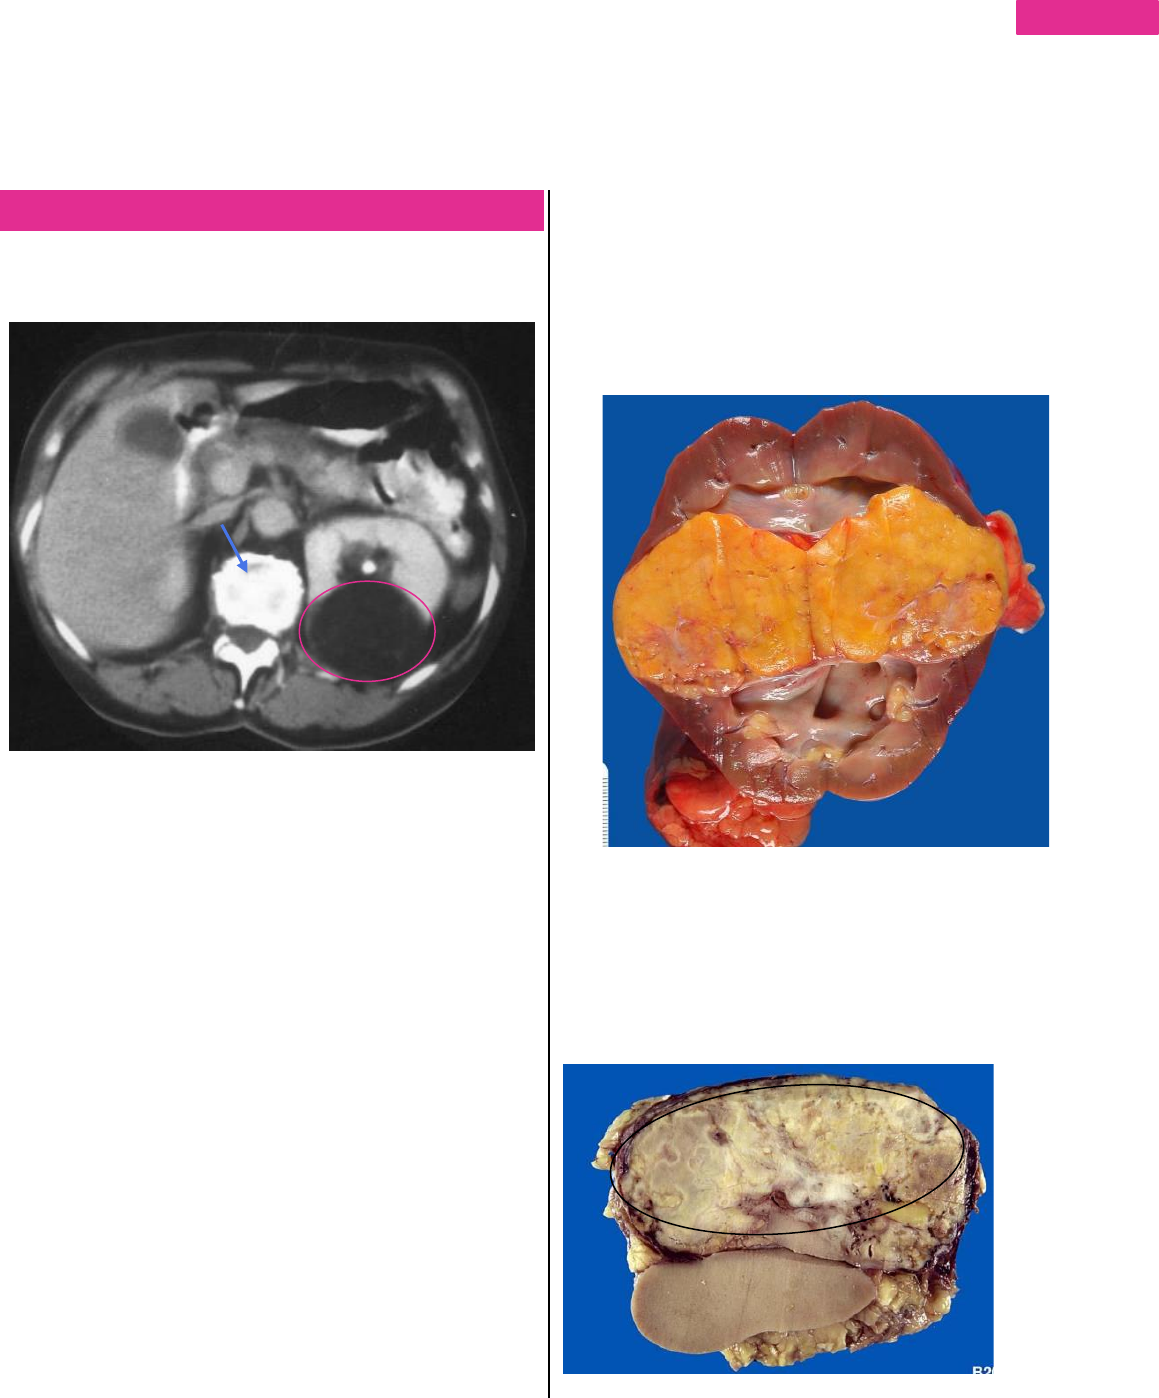

o Mulher de 26 anos apresentando massa renal de 4,0

cm. Observe as imagens e diga o diagnostico

Em rosa vemos uma lesão de baixa densidade, bem

delimitada no rim Esquerdo, não sendo tão radiopaca e com

consistência de tecido entre a pele e o tecido muscular (não

em consistência ou aspecto de gas porque é hipodenso).

Seta azul – estrutura radiodensa com aspecto ósseo

calcificado (provavelmente um calculo fora da lesão).

Com a retirada do rim temos esse tumor bem delimitado

(limites nítidos entre tumor e o parênquima) com superfície

regular, homogênea (amarelada) e com algumas áreas

esbranquiçadas (pode ser uma estrutura vascular) e o rim

está preservado (região medular mais branca, cálices e

córtex). Tumor com efeito de massa, amarelado.

Abaixo vemos tumor (circulado) com aspecto diferente após

a fixação, com coloração esbranquiçada/acastanhada,

heterogêneo porem não perde a nitidez e a delimitação

entre parênquima e tumor.